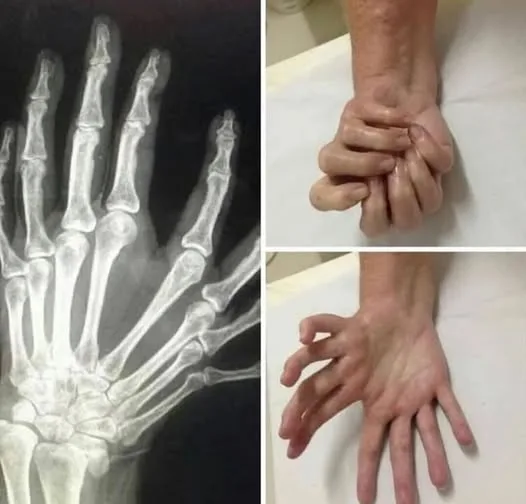

The images reveal one of the rarest congenital anomalies in medical history: ulnar dimelia, commonly known as mirror hand. This condition transforms a human hand into a perfectly symmetrical, seven- or eight-fingered structure with no thumb, where the ulna (forearm bone) is duplicated, the radius is absent, and the wrist contains twice the normal number of carpal bones. Metacarpals and phalanges are mirrored along a central axis, creating a hand that looks as if it has been reflected in a mirror. Most astonishingly, the tendons are cross-connected: when one finger flexes, its mirror opposite moves in perfect synchronization, producing an eerie, symmetrical motion.

The hand typically features:

- 7–8 fingers (polydactyly) of roughly equal length.

- No thumb—all digits resemble ring or middle fingers.

- Duplicated ulna, absent radius.

- Mirrored tendon arrangement, causing symmetric movement.

Function varies: some individuals have surprisingly good grip despite the lack of opposition, while others require surgical modification.

First formally described in the 19th century, early cases were often sensationalized as “monstrosities.” Modern surgery can reconstruct a more functional hand by removing central digits and creating a thumb, but many affected individuals—especially in cultures where the condition is accepted—live without intervention. The mirrored motion, where flexing one finger forces its twin to mirror the action, has fascinated neurologists studying tendon mapping and motor control.